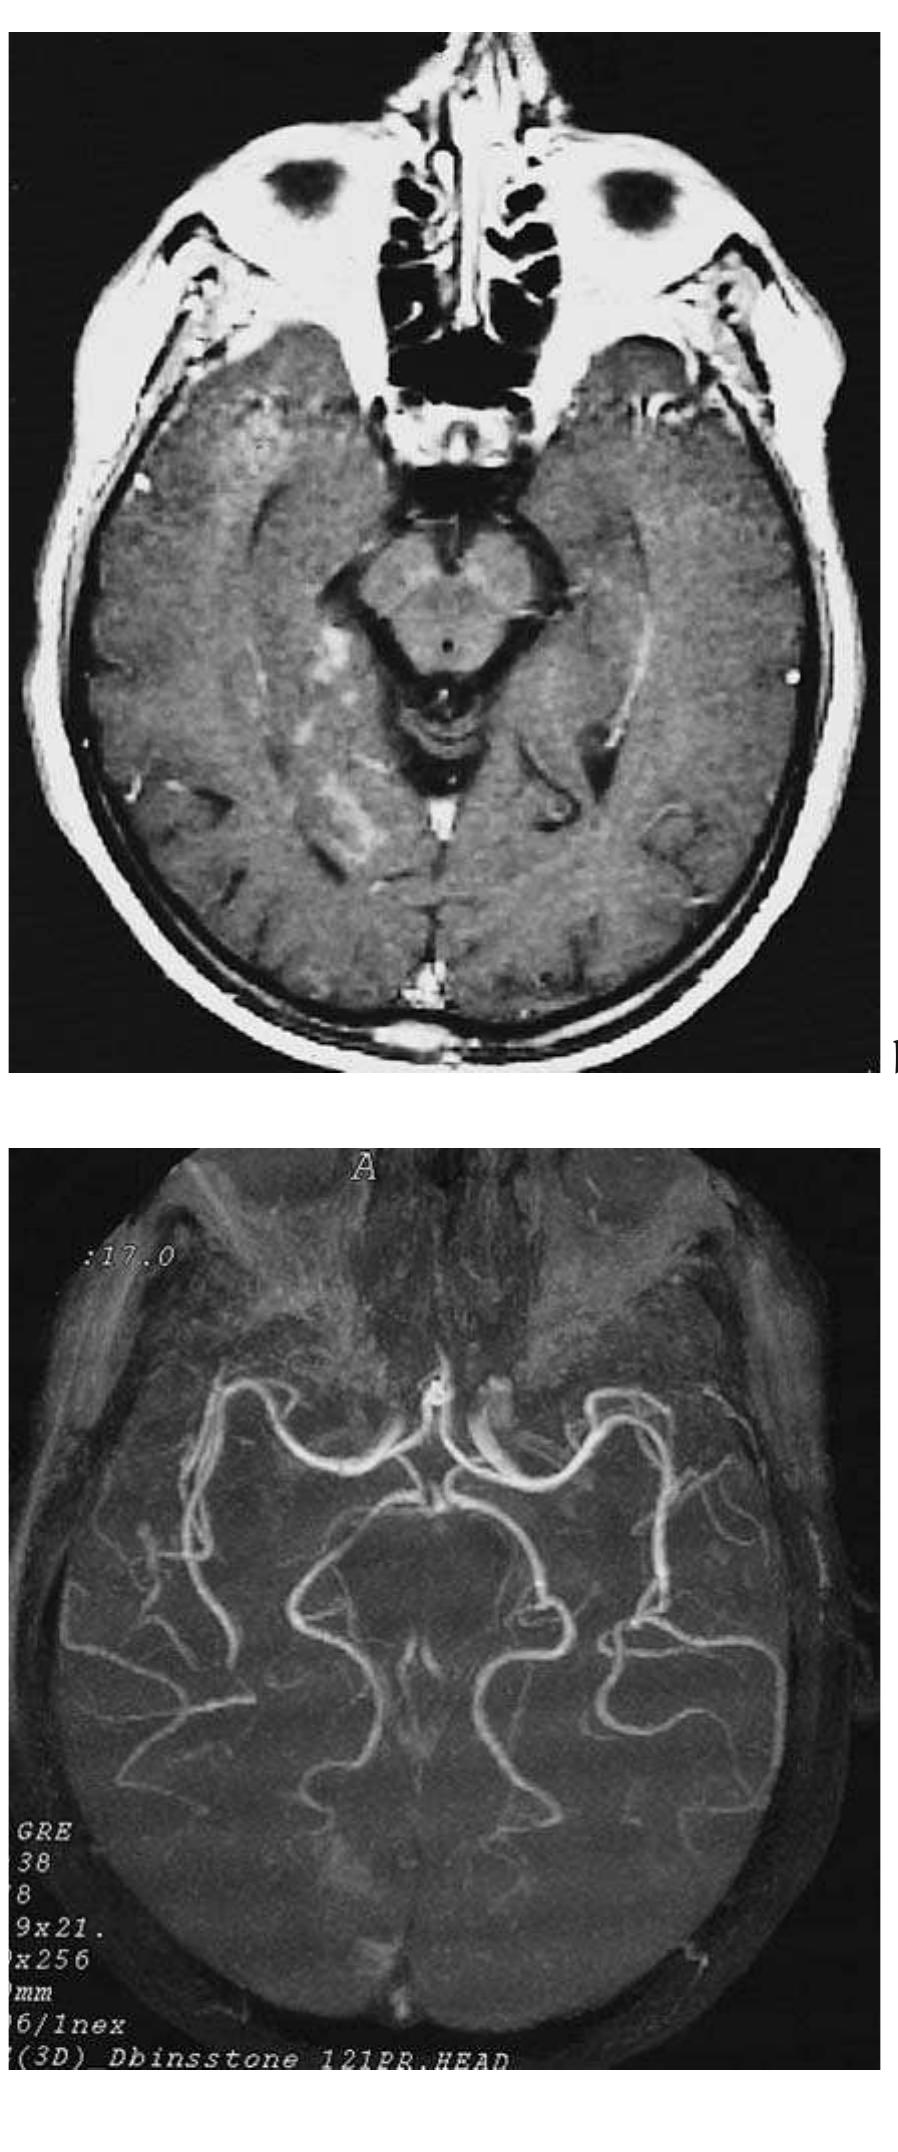

![Fig. 2.24 - Posttraumatic cerebral swelling. The CT demon- strated diffuse posttraumatic cerebral swelling is seen with obliteration of the basal subarachnoid cisterns and superficial cortical sulci, compression of the 3" ventricle and reduction in size of the lateral ventricles. The midline structures are not shifted, and there are no focal haemorrhages are present. [a), b), c) axial CT].](https://figures.academia-assets.com/35610716/figure_163.jpg)